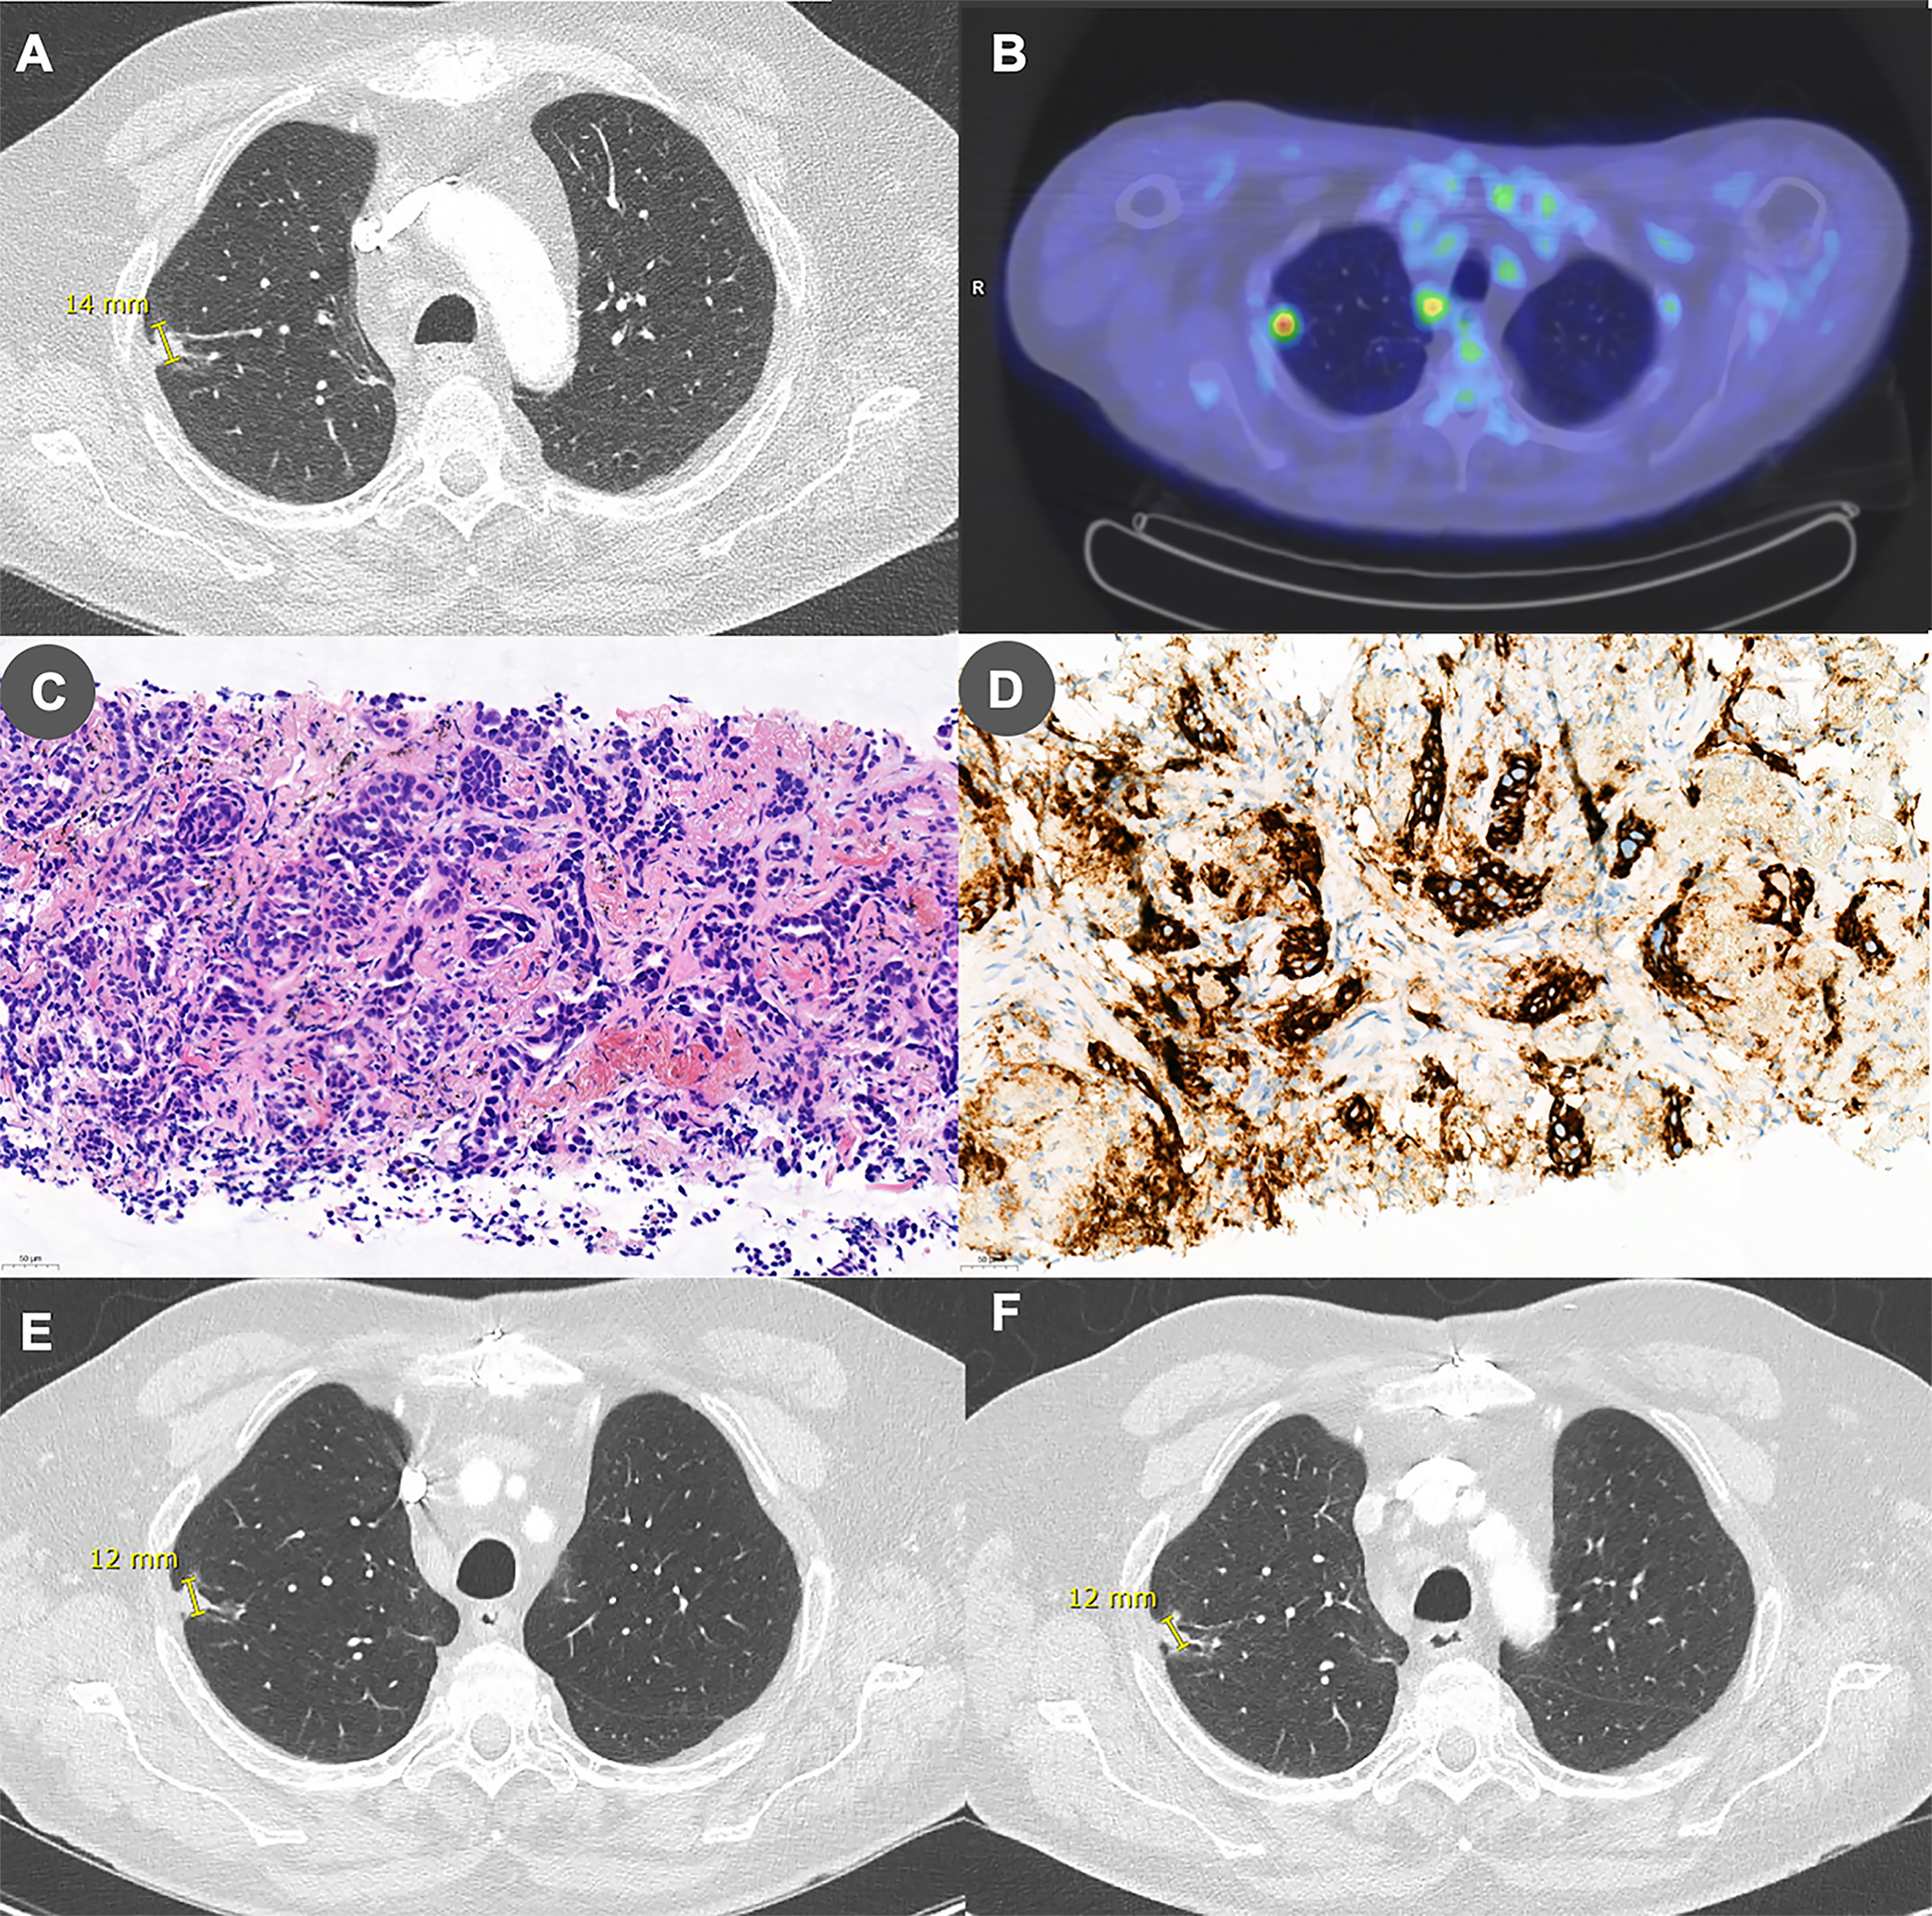

Complete blood count and flow cytometry were performed to search an underlying immune deficiency and revealed lymphopenia affecting predominantly CD4+ T cells (530 lymphocytes/μL including 140 CD4+ cells/μL, 210 CD8+ cells/μL, and 100 CD19+ cells/μL). Human immunodeficiency virus (HIV) serology was repeatedly negative on two separate samples. Whole-body [18F]-fluorodeoxyglucose positron emission tomography (18FDG-PET) and associated chest computed tomography (CT) revealed a 1.4 cm hypermetabolic nodular and irregular mass located at the lateral edge of the right upper lobe associated with ipsilateral hilar, paratracheal and subcarinal hypermetabolic lymphadenopathy (Figures 2A, B). Lung CT-guided biopsy was performed, and pathological analyses were consistent with the diagnosis of lung adenocarcinoma (Figure 2C). PD-L1 was expressed by 50% of tumor cells (Figure 2D). Anaplastic lymphoma kinase (ALK) and ROS1 immunohistochemical analyses were negative. We found no mutation in EGFR gene and next-generation sequencing (NGS) assay only found a MET mutation with no clinical impact. The patient was eventually diagnosed with PML in a context of stage IIIA (T1bN2M0) NSCLC according to the eighth American joint committee on cancer classification.

Figure 2

Panel (A) Chest CT performed before treatment initiation showing a 14-mm right upper lobe irregular nodular lesion. Panel (B) This lesion was found to be hypermetabolic on [18F]-fluorodeoxyglucose positron emission tomography. Panel (C) Lung biopsy specimen showing a modified fibrous tissue infiltrated by irregular and ramified tubuloacinar structures formed by non-small neoplastic cells with hyperchromatic nucleus and weakly eosinophilic cytoplasm. The overall appearance is compatible with a lung adenocarcinoma (hematoxylin-eosin stain, 200x). Panel (D) PD-L1 is expressed by 50% of tumor cells (PD-L1 immunoperoxydase, 200x). Panels (E, F) Chest CT performed (E) 6 months and (F) 1 year after treatment initiation showing stability of the lesion.

The patient was discharged to a revalidation center, where he continued to improve gradually. CSF JCV load reduced accordingly and was even below the PCR’s detection limit (75 copies/mL) 9 months after treatment initiation (Figure 1C). Brain MRI showed regression of the extent of the T2-FLAIR lesions and disappearance of DWI signs of disease activity (Figure 1B and Supplementary Figure S1). Regarding lung adenocarcinoma, repeated thoracic-abdominal-pelvic CTs demonstrated a stable disease (Figures 2E, F).